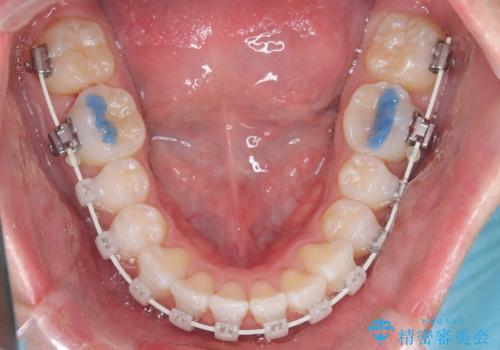

- ワイヤー(審美装置)

- 11ヶ月

左側は2級傾向が強く臼歯の遠心移動をご提案しましたが、1年以内に矯正を終わらせたいという患者様のご意向で希望されず叢生を改善する矯正となりました。